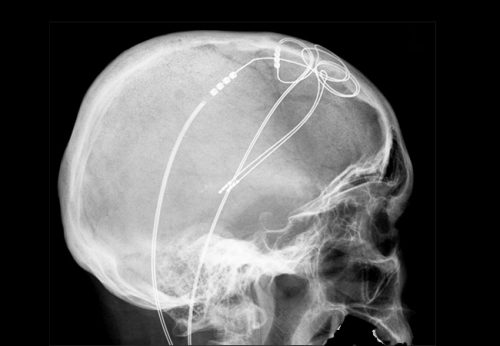

Foto: Hellerhoff, Wikimedia, CC BY-SA 3.0

Durch Kells Forschungsarbeiten wurde ein junger Mensch, der stark stotterte, auf ihn aufmerksam. Er wollte nach seinem Studium unbedingt einen Beruf verfolgen, in dem er viel kommunizieren muss. Der Mann sagte, er habe alle möglichen Therapien durchgemacht und kein zufriedenstellendes Ergebnis erreichen können. Kell und seine Kooperationspartner rund um Prof. Katrin Neumann an der Universität Münster würden doch europaweit zu dem Thema forschen. Er brauche von ihnen eine Therapie und wolle einen Hirnschrittmacher haben.

Das Team lehnte ab, jahrelang, denn eine sogenannte tiefe Hirnstimulation war bislang noch nie mit dem Ziel gemacht worden, Stottern zu reduzieren. Vielmehr handelt es sich um eine Therapie, die zum Beispiel bei Zitter-Erkrankungen wie Morbus Parkinson angewandt werden kann. Hier kann – mit dem Risiko unerwünschter Nebenwirkungen – mithilfe dauerhaft eingepflanzter Elektroden über leichte Ströme in vielen Fällen das Zittern drastisch reduziert werden.

Der junge Mann blieb hartnäckig, und schließlich entwickelten Kell und das Münsteraner Team auf Basis der wissenschaftlichen Literatur und eigener Arbeiten eine so überzeugende Hypothese, dass Ethikkommission und Neurochirurgen einwilligten und dem Stotternden eine Elektrode zur tiefen Hirnstimulation implantiert wurde.